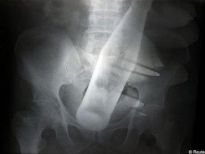

Şoke eden röntgen filmleri

Bu röntgen filmleri görenleri şaşkına çeviriyor!